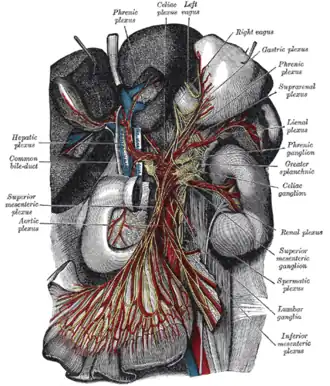

The celiac ganglia with the sympathetic plexuses of the abdominal viscera radiating from the ganglia

The celiac ganglia with the sympathetic plexuses of the abdominal viscera radiating from the ganglia -

Upon leaving the medulla oblongata between the olive and the inferior cerebellar peduncle, the vagus nerve extends through the jugular foramen, then passes into the carotid sheath between the internal carotid artery and the internal jugular vein down to the neck, chest, and abdomen, where it contributes to the innervation of the viscera, reaching all the way to the colon. Besides giving some output to various organs, the vagus nerve comprises between 80% and 90% of afferent nerve fibers conveying sensory information about the state of the body's organs to the central nervous system.[4]

Right Vagus Nerve: The right vagus nerve gives rise to the right recurrent laryngeal nerve, which hooks around the right subclavian artery and ascends into the neck between the trachea and esophagus. The right vagus then crosses anterior to the right subclavian artery, runs posterior to the superior vena cava, descends posterior to the right main bronchus, and contributes to cardiac, pulmonary, and esophageal plexuses. It forms the posterior vagal trunk at the lower part of the esophagus and passes through the diaphragm to enter the abdomen through the esophageal hiatus.

Left Vagus Nerve: The left vagus nerve enters the thorax between left common carotid artery and left subclavian artery and descends on the aortic arch. It gives rise to the left recurrent laryngeal nerve, which hooks around the aortic arch to the left of the ligamentum arteriosum and ascends between the trachea and esophagus. The left vagus further gives off thoracic cardiac branches, breaks up into the pulmonary plexus, continues into the esophageal plexus, and enters the abdomen as the anterior vagal trunk by way of the esophageal hiatus of the diaphragm.

The vagus nerve supplies motor parasympathetic fibers to all the organs (except the adrenal glands) from the neck down to the second segment of the transverse colon. The vagus also controls a few skeletal muscles, including:

This means that the vagus nerve is responsible for such varied tasks as heart rate, gastrointestinal peristalsis, sweating, and quite a few muscle movements in the mouth, including speech (via the recurrent laryngeal nerve). It also has some afferent fibers that innervate the inner (canal) portion of the outer ear (via the auricular branch, also known as Arnold's or Alderman's nerve) and part of the meninges.[10] The vagus nerve is also responsible for regulating inflammation in the body, via the inflammatory reflex.[11]

Cardiac effects

Parasympathetic innervation of the heart is partially controlled by the vagus nerve and is shared by the thoracic ganglia. Vagal and spinal ganglionic nerves mediate the lowering of the heart rate. The right vagus branch innervates the sinoatrial node. In healthy people, parasympathetic tone from these sources is well-matched to sympathetic tone. Hyperstimulation of parasympathetic influence promotes bradyarrhythmias. When hyperstimulated, the left vagal branch predisposes the heart to conduction block at the atrioventricular node.